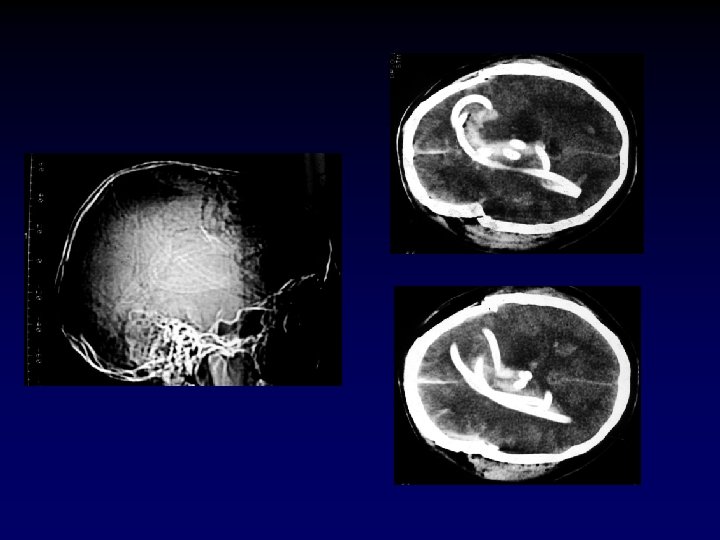

Case Presentation • 25 year old male presents s/p single stab wound to the left chest. He clearly smells of alcohol and is lethargic – responding only to painful stimuli. Field vitals are P 150, BP 80/palp, Resp 35. • What’s the plan? ?

Indications • Inability to oxygenate – Pa. O 2/Fi. O 2 < 200 • Inability to ventilate – Respiratory rate > 30 or < 5 – PCO 2 > 60 • Inability to protect airway – GCS ≤ 8